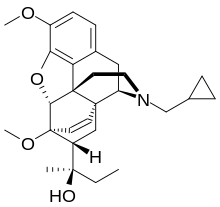

Oripavine derivatives

Thienorphine

- 7-PET

- Acetorphine

- Alletorphine (N-allyl-noretorphine)

- BU-48

- Buprenorphine

- Buprenorphine-3-glucuronide

- Cyprenorphine

- Dihydroetorphine

- Etorphine

- Homprenorphine

- 18,19-Dehydrobuprenorphine (HS-599)

- N-cyclopropylmethylnoretorphine

- Nepenthone

- Norbuprenorphine

- Norbuprenorphine-3-glucuronide

- Thevinone

- Thienorphine

Structures

| Oripavine derivatives | ||||

|---|---|---|---|---|

7-PET 7-PET |

Acetorphine Acetorphine |

Alletorphine Alletorphine |

BU-48 BU-48 |

Buprenorphine Buprenorphine |

Cyprenorphine Cyprenorphine |

Dihydroetorphine Dihydroetorphine |

Etorphine Etorphine |

Homprenorphine Homprenorphine |

18,19-Dehydrobuprenorphine 18,19-Dehydrobuprenorphine |

N-cyclopropylmethylnoretorphine N-cyclopropylmethylnoretorphine |

Nepenthone Nepenthone |

Norbuprenorphine Norbuprenorphine |

Thevinone Thevinone |

Thienorphine Thienorphine |